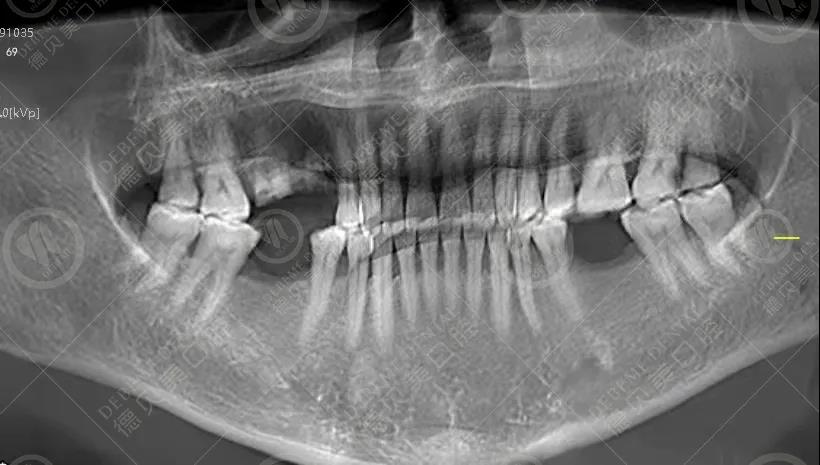

牙科诊疗,往往是一场小型的外科手术。看牙拍片,是为了更全面地了解牙齿的情况,确定治疗范围、治疗深度。以最常见的拔牙为例,没有拍片检查,牙医怎么知道牙根是2个、3个、4个?是弯曲的还是粗壮的?需不需要开刀?

补牙、拔牙、种牙、矫牙、根管治疗等常见的操作,都需要拍片检查。